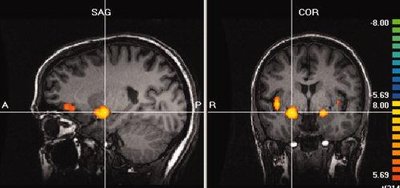

Functional MRI of Olfactory Activation

Functional MRI studies show that olfactory stimulation activates the amygdala, insular cortex, and orbitofrontal cortex. These regions are involved in emotional processing, integration of sensory information, and conscious odor perception.

Bilateral amygdala activation reflects the emotional impact of odors.

Insular and orbitofrontal cortex activation is associated with complex processing and discrimination of odors.